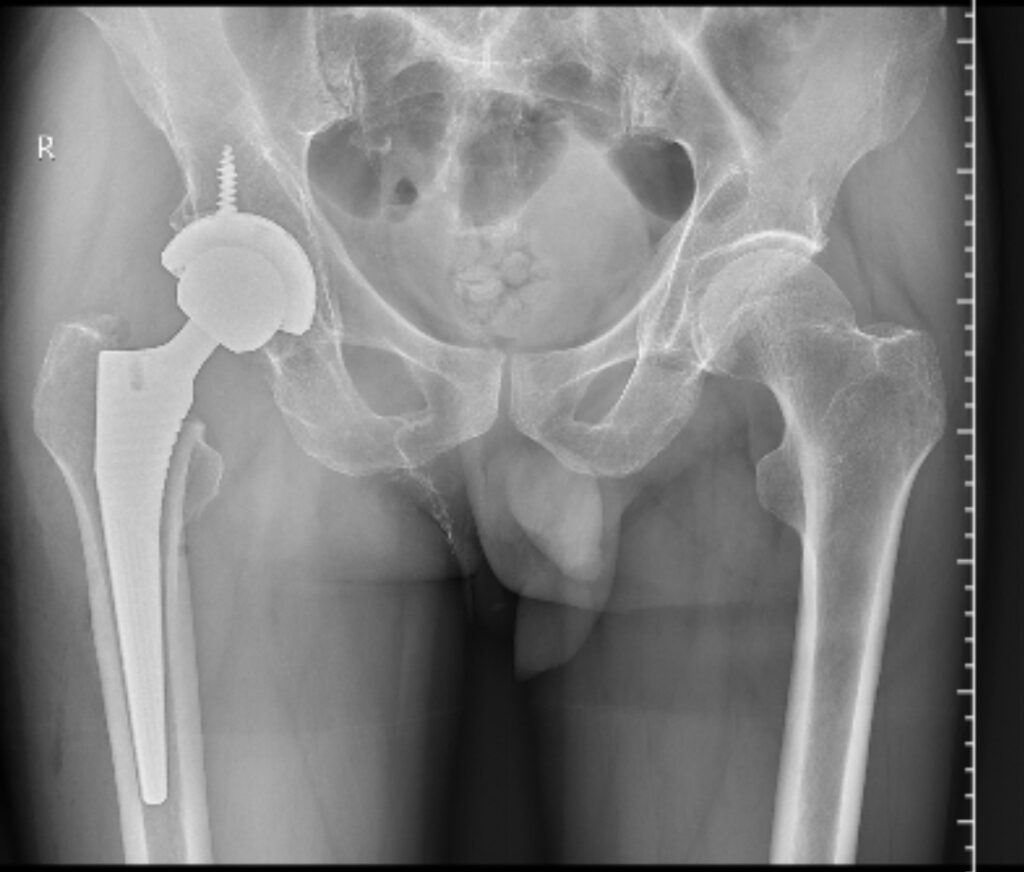

全髋术后股骨侧假体周围骨折切开复位内固定股骨柄翻修术(Open reduction, internal fixation and femoral stem revision for periprosthetic fractures on the femoral side after total hip surgery)